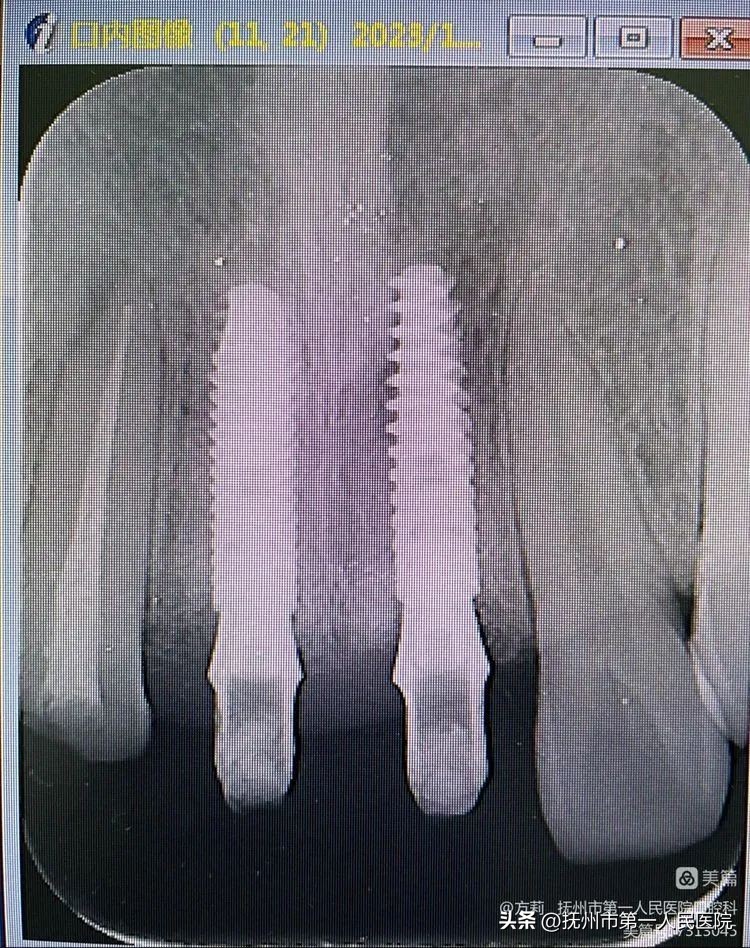

图中展示,患者穿龈轮廓及牙龈塑型良好

患者术后20个月根尖片影像显示:11、21无明显骨嵴吸收!

进行临时义齿个性化取模,准备制作永久修复体!